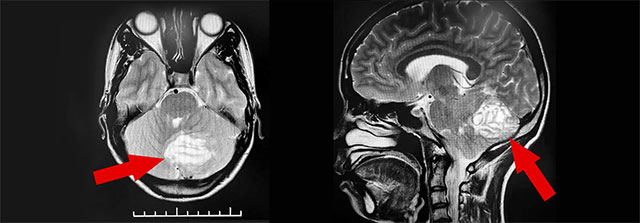

虽然属于相当少见的疾病,但小脑发育不良性神经节细胞瘤较易获得明确诊断。沈教授表示,小脑发育不良性神经节细胞瘤的主要检查方法是磁共振成像(MRI),MRI能清楚显示小脑发育不良性神经节细胞瘤的条纹状或分层状改变表现,即所谓的“虎纹征”——这对小脑发育不良性神经节细胞瘤具有术前定性诊断价值。

▲ MRI检查显示,该小脑肿瘤有明显的“虎纹征”